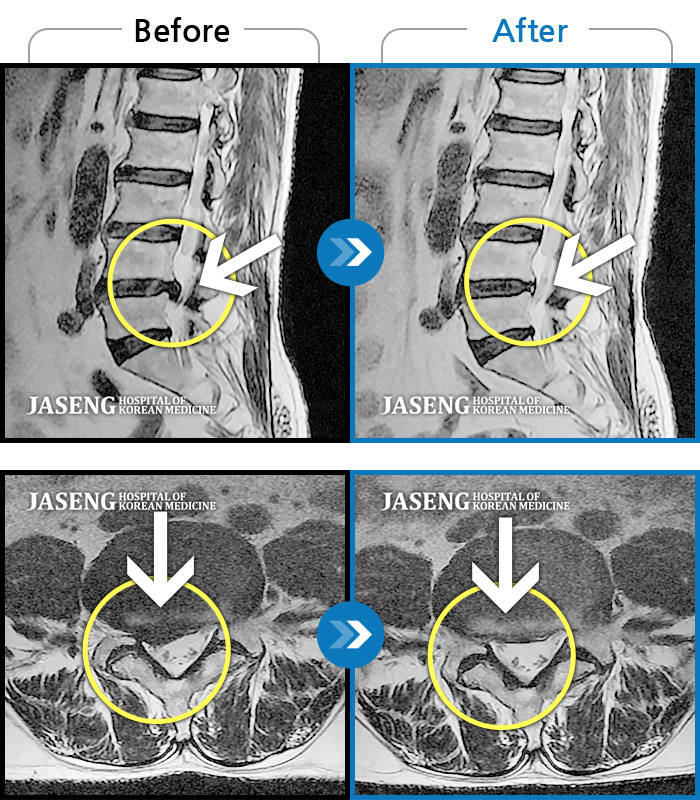

일산자생 한방 병원 한방진료팀 정승현 원장님과 담당 간호사분들께 감사드립니다. 지난해 11월 첫 병원 내원시에는 디스크가 터져서 허리와 다리통증이 심해서 의자에 앉기도 힘들 정도의 몸상태였습니다. 거리가 있어서 꾸준하게 통원치료 받는것이 힘들고 부담이 되었지만 늘 친절히 진료해주셔서 1차 3개월 치료를 받으니 어느정도 통증은 감소되었고, 2차 3개월 치료를 받고 MRI 사진으로 완치 판정을 받았습니다. 내원할때마다 차근히 상태 설명해주시고 치료해 주셔서 믿음을 가지고 꾸준히 치료받은 결과 전보다 보행도 더 편하고 허리상태도 정말 많이 좋아짐을 느낍니다. 원장님과 수고해주신 간호사님들께 다시한번 감사드립니다.